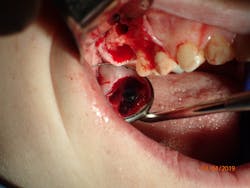

As direct implant costs have gone down, the simplification and efficiency of many implant procedures have contributed to what many are calling the “golden age of implant dentistry.” The advent of short implants—and research articles backing the success rate of short implants—has reduced the need for more extensive grafting procedures. This is one clinical area that has allowed more general practitioners to place more implants due to the simplified sinus-area procedures. In areas of 6 mm or more of maxillary bone height, clinicians are able to provide a minimally invasive sinus bump and achieve bicortical stabilization. Implants such as the iHex and MorsTorq were designed with a rounded end to safely provide this procedure. The taper of these and similar systems also protects the implant from being lodged apically into the sinus cavity, thus making it user-friendly for beginner to intermediate implantologists.

Therefore, if a patient has 5 mm of available bone height from the sinus floor, a maximum of 5 mm is prudent to expect from an indirect lift; therefore, an 8 mm to 10 mm implant is the ideal choice. The tapered iHex or MorsTorq implant provides safety when dealing with sinus areas, for three reasons. First, the taper helps prevent overinsertion toward the sinus cavity. Second, the abutment and transfer attached to the implant allows for more control. Finally, the rounded apex helps reflect the sinus floor without creating damage (figures 1-6).